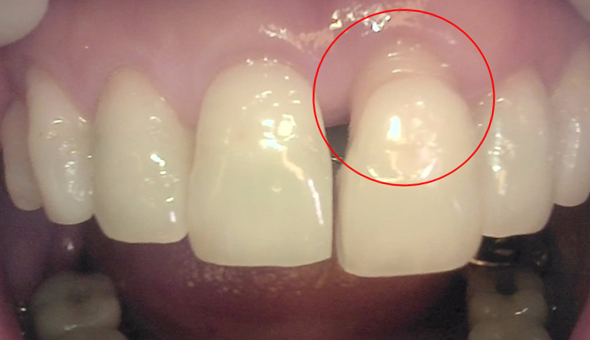

이처럼 잇몸뼈가 퇴축된 경우, 임플란트 치아 길이가 위아래로 길어져 심미성이 떨어지게 됩니다. 추가적인 잇몸이식을 통하여 잇몸의 길이를 확보해 주어야 하는 경우였지만, 환자분께서 잇몸이식을 두려워 하셨고 우선 잇몸 이식 없이 임플란트를 시행하되, 임시치아의 모양을 보면서 차후에 추가적인 잇몸이식을 시행하는 것으로 치료계획을 세웠습니다.

자세하게 보지 않으면 모를 정도로 차이가 미세해서 잇몸이식 없이 치료를 완료하였습니다.